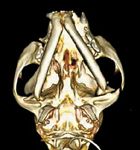

The lower jaw of the cat on your exam table is displaced to the left (Photo 1). Is the mandible or maxilla fractured? Or is the mandible luxated? If so, right or left? What is the best way to diagnose and treat this problem? Can you as a general practitioner handle it, or must the case be referred to a boarded orthopedic or dental specialist?